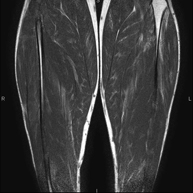

Exploració per estudiar la musculatura i dels tendons que s'originen en aquest nivell, com els tendons isquiotibials, lesió sovint en esportistes. La durada aproximada és de 16 minuts. No empra radiació ionitzant. - RM de Cuixa

Exploració ideal per estudiar les lesions en músculs isquiotibials i quàdriceps, sovint lesionats en esportistes. També permet una bona valoració de tendons i de nervis perifèrics. La durada aproximada és de 20 minuts. No utilitza radiació ionitzan. - RM de Genoll

Prova diagnòstica no invasiva que consisteix en l'obtenció d'imatges d'alta definició anatòmica de la musculatura que s'estudia mitjançant l'ús d'un camp electromagnètic i ones de ràdio (amb un emissor i un receptor). No utilitza radiació ionitzant. Poques vegades requereix l'ús de contrast paramagnètic (Gadolini) per a una millor definició de les lesions. - RM d'Ossos i articulacions